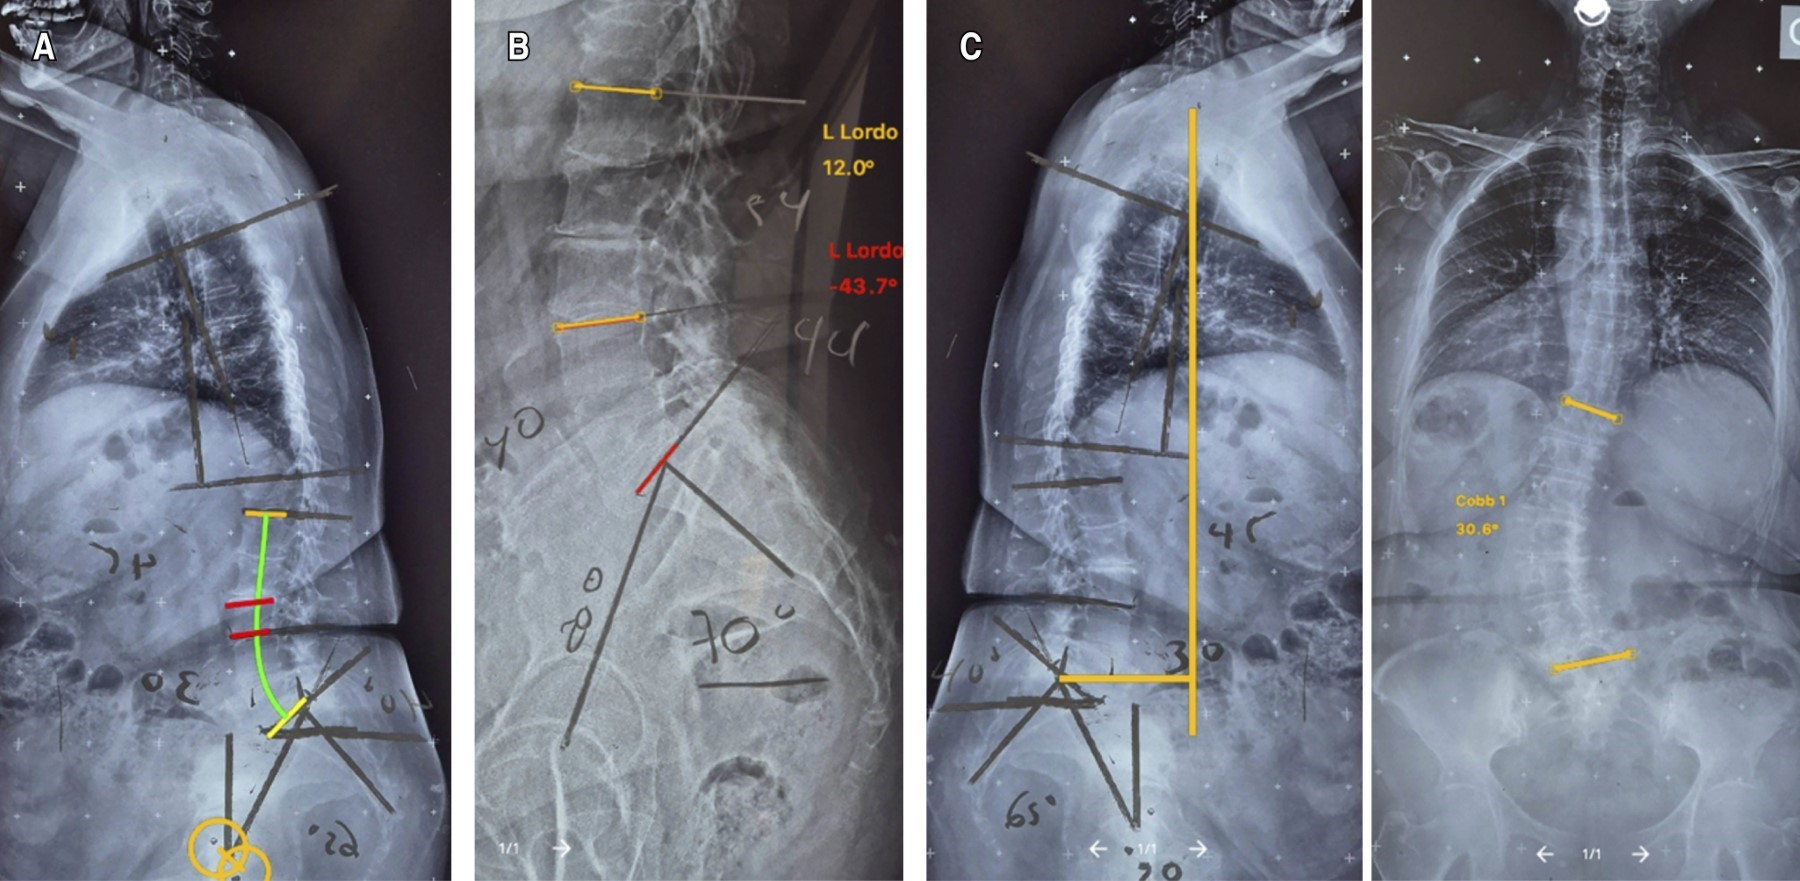

Figure 4